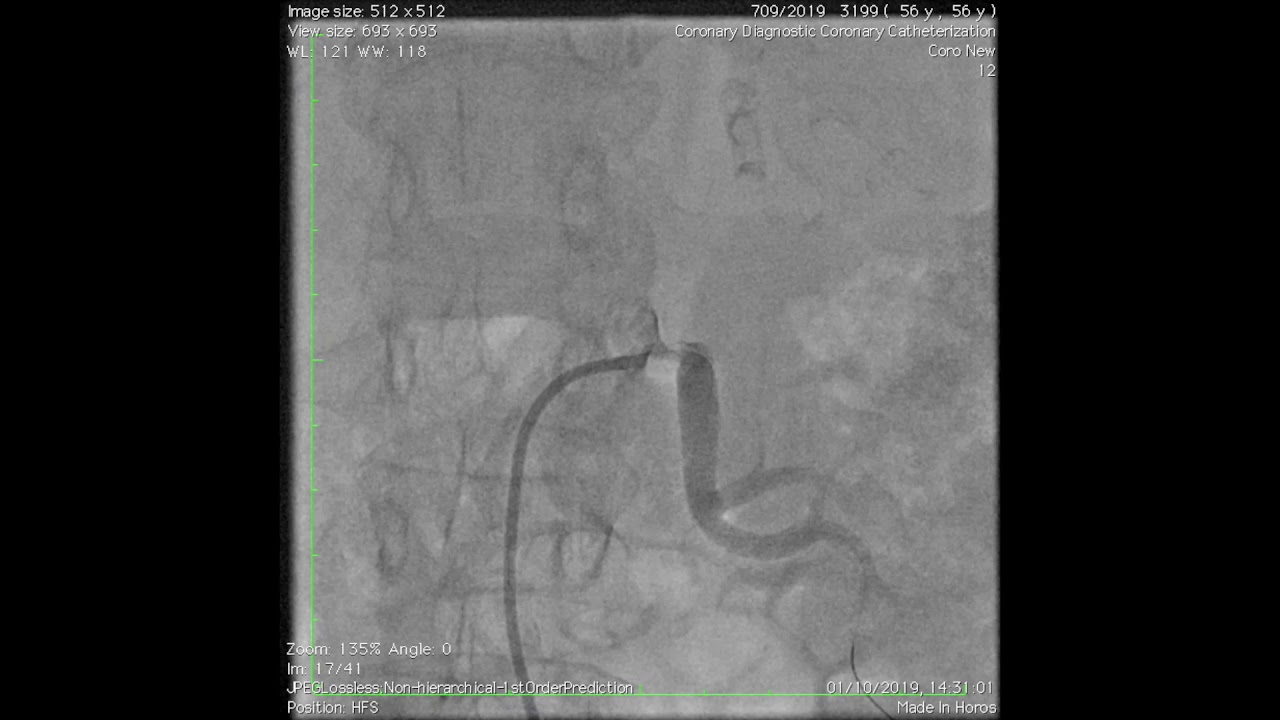

Sono un Cardiologo specializzato nella Cardiologia Interventistica, con grande interesse nel trattamento percutaneo delle patologia Cardiache e Vascolari (Coronaropatie, Arteriopatie ostruttive degli arti inferiori e malattia Aterosclerotica Carotidea).

• Angiografia

• Angioplastica

• Coronarografia